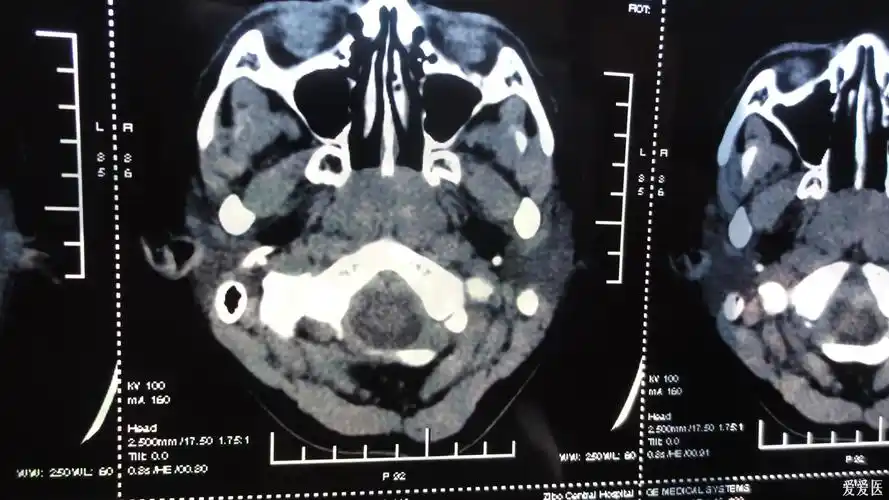

儿童腺样体肥大丨识别与诊治,x线测量方法_增殖腺

腺样体肥大是一种常见的儿童疾病,也称为咽扁桃体肥大或增殖体肥

data-id="gnaorkug1f">增殖腺(adenoid)是位于鼻咽部的一种特殊腺体